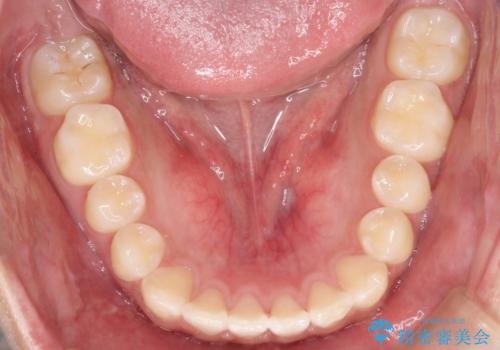

- 前歯のがたつきを主訴に来院されました。

上顎の前から2番目の歯の噛み合わせが反対になっていました。

抜歯矯正も考えられるケースでしたが、非抜歯での矯正を希望され、インビザラインにて治療することとなりました。

目立たずに矯正を終えることができ、患者様にも満足していただきました。